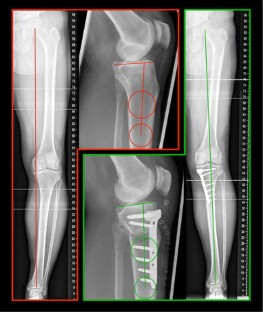

Fig. 2